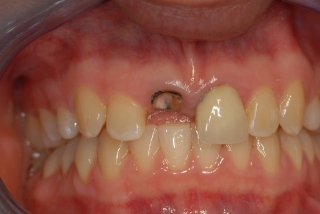

Dental Implant Videos

Videos related to treatment planning and placement of dental implants